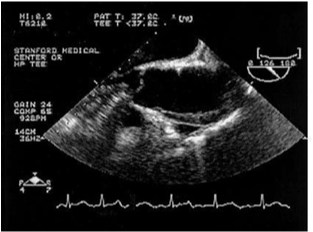

Figure 6 Ascending aorta showing intramural hematoma of the anterior wall of the ascending aorta.29

Figure 7 Ascending aorta showing the position of the stent after deployment.29

In contrast, Echo Doppler has been recognized as a good option to these techniques due to its low cost, easy implementation and interpretation and the absence of exposure to any type of radiation.26 This provides a better understanding of the endoleak formation mechanism and provides a more accurate analysis thereof, due to a collateral circulation. The origins of an endoleak may also be correctly identified. Compounded by the fact that it allows visualize blood flow in the aneurysm sac and its direction. This seems to be an excellent tool in the evaluation of high flow endoleaks within the aneurysmal sac. It is an imaging technique commonly used in vascular studies, being easy to perform, inexpensive, portable, secure and highly available. Its use for patients’ follow-up can reduce the biological hazards associated with CT angiography, since this frees the body of the individual to a substantial dose of ionizing radiation. The advantage of Doppler ultrasound in patients’ follow-up with aortic stent graft is that it allows a serial measurement over time of the residual diameter of the aorticaneurysm sac. Doppler ultrasound is more accurate than CT for the detection of problems associated with stent graft patency, their migration, kinking and stenosis. Provides physiological and anatomical information at the same time, unlike CT. The ability to quantify and compare serial images at a low cost without contrast and radiation, suggests that this technique should be the Gold Standard in the follow-up to TEVAR (Figures 5-9).20,24,27